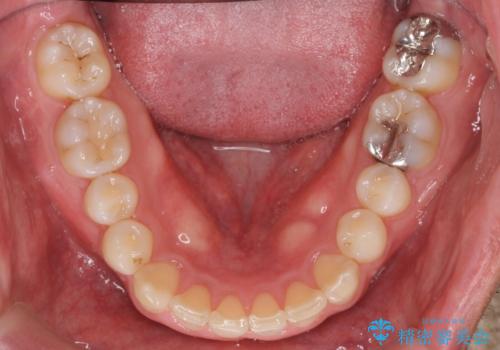

深い噛み合わせと上顎前突の状態を治すのに時間がかかりましたが、治療後は理想的で安定した咬合関係となりました。